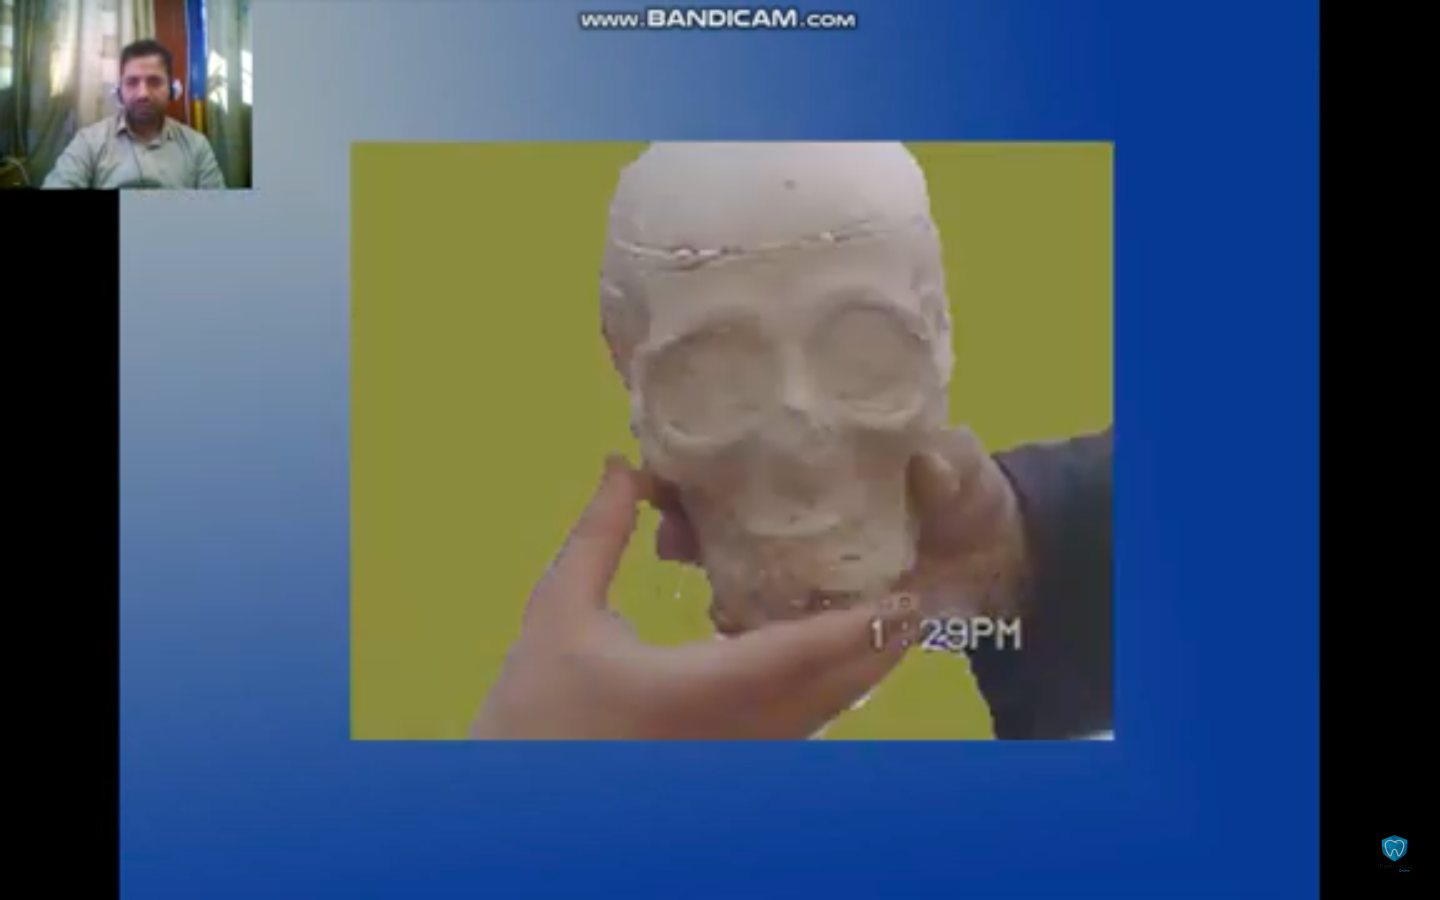

—the tear; a video loop offering at 1:29

—the tear; a video loop offering at 1:29

The (I) of this book falls into a forensic obsession following the threads of a clinical study in which two corpses get mysteriously entangled in Hama, Syria, 2008: The material corpse of an unknown Syrian woman and the bureaucratic corpse of a missing Canadian citizen, Jacqueline Nicole Vienneau.

I got to know this forensic case study during my medical education in Damascus university. The case study is mentioned in forensic medicine as an example of the first and only case of identification in which a Syrian forensic team does a facial reconstruction of an unknown corpse found in Hama in 2008.

Blending the disappearance of an unnamed Syrian woman with mythical poetry and the desire to reconstitute her face which keeps melting between the fingers of a book.